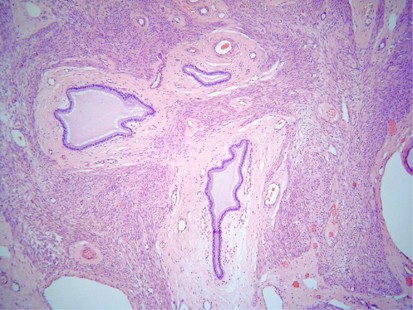

Histologically, the mixed nature of the tumour is exemplified by the presence of both epithelial and stromal elements, the latter predominating. At low power magnification, the tumour often has a phyllodes-like (leaf-like or club-like) architecture (Figure 7). The epithelial elements usually consist of glands, which may be dilated or slit-like with a phyllodes-like appearance, lined by cuboidal or low columnar cells. In most cases, the epithelium is endometrioid and resembles proliferative endometrium, although ciliated, mucinous and squamous epithelium may also be seen. Uncommonly, the epithelial component exhibits glandular complexity resembling atypical hyperplasia/endometrial intraepithelial neoplasia or carcinoma. The latter is usually a low-grade endometrioid carcinoma.28 The stromal component, which is typically low grade, is composed of spindled and/or round cells with scant cytoplasm, but rarely can be high grade. Intraglandular protrusions of stroma and the manner in which the stromal cells, which often resemble endometrial stromal cells, concentrate around or beneath the glandular elements (‘periglandular cuffing’) are characteristic (Figure 8). The ‘cuffing’ may be very thin (and thus overlooked) but is where nuclear atypia and mitotic activity are typically found (Figure 9). Although a mitotic rate of ≥2 per 10 high power fields (HPFs) is often seen, some tumours have a lower mitotic rate and should be diagnosed as adenosarcoma if the tumour has the characteristic aforementioned features as reflected in the 2014 WHO classification.1

Adenomyomas of endocervical type are uncommon neoplasms, and usually occur in women of reproductive or postmenopausal age.72, 73 They vary in size and are most commonly polypoid and project from the mucosal surface of the cervix. Rarely, they may be intramural or exophytic but are always grossly well circumscribed, usually grey-white to tan and may contain small cysts. Histologically, they are composed of bland mucinous glands of endocervical type, often with a somewhat lobular arrangement, embedded in a stroma containing abundant smooth muscle (Figure 15). Some of the glands may be dilated. Tubal, endometrioid or squamous epithelium may be occasionally seen. There is often a thin rim of fibrous tissue surrounding the glands, which is in turn surrounded by mature smooth muscle. Other findings, which are occasionally seen, include gland rupture with mucin extravasation, small intraglandular papillary proliferations (adenofibroma-like) and symplastic change in the smooth muscle component.72, 73 These are benign lesions but occasionally persist or recur following local excision.